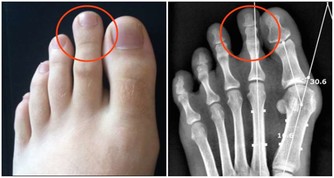

熱痙攣

通常發生在人進行劇烈運動目大量出時,人身體中的鹽分和水分隨汗液一同流失。肌肉中的含鹽量低可能是造成熱痙攣的原因。此外,停攣也可能是熱衰竭的一種表現。

1怎樣識別

表現為肌肉或抽描,發生在腰部手臂或部。常呈對稱性,時而發作。患者意識醒,體溫一般正常。